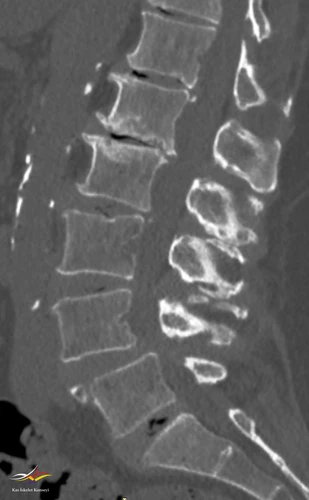

Resim 2. Lomber BT incelemesi.